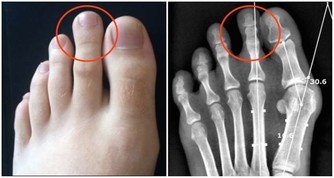

1. 他的身體某個部位很痛

雖然這種說法聽起來很寬泛,但至關重要。衰老可以欺騙男人認為“痛苦是正常的”。然而,任何一種關節疼痛都可能很快開始影響他的生活質量,背部疼痛可能會讓他特別虛弱。

更要命的是,疼痛可能是癌症的徵兆,雖然這種情況很少。但診斷疼痛的來源,將有助於讓你的身心得到休息。

比如,睾丸癌是罕見的,但在40歲以下的男性中最常見。如果他抱怨陰囊疼痛無力或感覺沉重,應該檢查一下。事實上,所有40歲以下的男性都應該進行睾丸檢查。